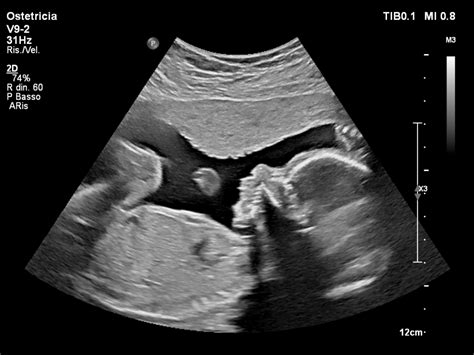

Le ecografie in gravidanza sono fondamentali non soltanto per capire se il bebè si è impiantato correttamente, se c'è abbastanza liquido amniotico e se cresce bene: grazie alle tecnologie di oggi, avanzatissime, è possibile studiare nel dettaglio ogni organo del feto e ogni sua caratteristica fisica. Le vie urinarie sono la parte anatomica tra le più interessate da anomalie, spesso congenite. Molte di queste sono diagnosticate già nei feti, durante la gravidanza, grazie all'ecografia del secondo trimestre, la cosiddetta morfologica, in cui vengono analizzati nel dettaglio gli organi.

Quando si parla di dilatazioni e anomalie renali nel feto il più delle volte si fa riferimento all'idronefrosi, cioè una dilatazione, appunto, delle pelvi e dei calici renali, che altro non è che un ristagno di urina nei reni. Questo tipo di anomalia è per la maggior parte benigna e viene individuata e monitorata nel corso della gravidanza. Di solito si vede durante l'ecografia del secondo trimestre e, se i valori dei bacinetti renali sono anomali, più grandi del dovuto, li si tiene sotto controllo.

Quella che capita più di frequente è la dilatazione delle pelvi (o bacinetti) renali, che normalmente sono cavità virtuali, dove l’urina scorre senza fermarsi, ma che si possono dilatare quando viene prodotta più pipì di quanta riesca a passarne oltre, nell’uretere e poi nella vescica; si comportano cioè più o meno come un palloncino elastico. È proprio questo limite di un centimetro quello che gli ecografisti considerano, nel feto, il confine fra normale e patologico, e così segnaleranno nel loro referto tutte le pelvi che appaiono più grandi. Attenzione, però: trovare dilatazioni anche più grandi di un centimetro non significa aver identificato una patologia; anzi alla stragrande maggioranza di queste dilatazioni non corrisponde alcun futuro problema per il bambino.

L'ecografia resta quindi l'esame di screening più sicuro anche per diagnosticare anomalie renali e dilatazioni, soprattutto per una diagnosi precoce. Le anomalie renali e del tratto urinario sono piuttosto frequenti e, il più delle volte, si risolvono senza esiti per il bambino dopo la nascita. Molto spesso, tra gli esami previsti in gravidanza, capita che, facendo un’ecografia di routine, venga segnalata un’alterazione dei reni o delle vie urinarie. Sono queste le anomalie renali di gran lunga più frequenti nei feti, ma dobbiamo chiarire subito che nella maggior parte dei casi si tratta di alterazioni innocue, di nessun significato per la salute del bambino, né nell’immediato, né in futuro.